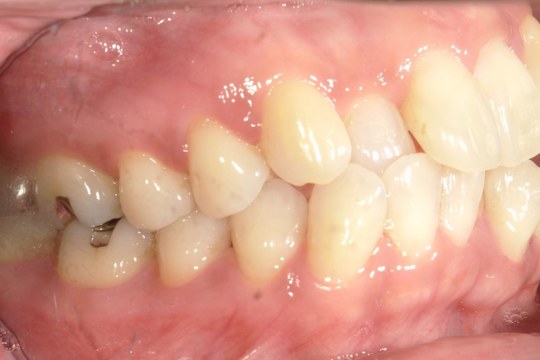

Before

浜松市中央区・自動車学校前駅のインビザラインの症例

K.M 20代女性

上の前歯が前方に出ていて横顔が気になるとの主訴でご来院。上下犬歯から犬歯までの6本が噛み合うよう、全体的に歯を内側に移動させることで、前歯の噛み合わせを整え叢生と開咬を治療しました。

​治療の期間:R5. 7/5〜R7. 1/17

​治療の価格:66万円